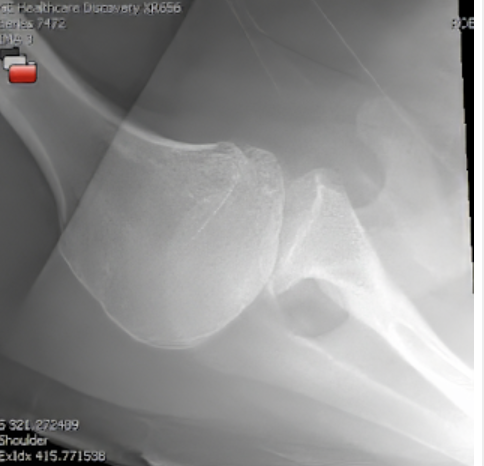

Four recently published articles provide important new information about the ream and run procedure for active patients with shoulder arthritis Those readers interested in learning more can access a discussion of these new articles here: shoulderarthritis.blogspot.com/2026/03/cocr-r…